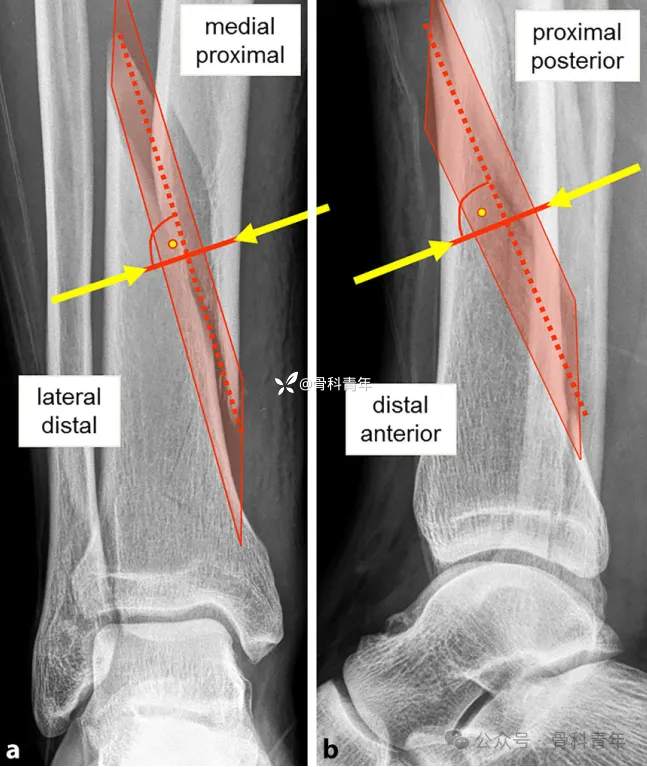

三、前/后成角畸形

与内外翻的手法复位类似,前后成角的复位通过踝关节的背伸与跖屈来完成: